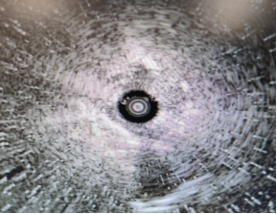

图3 术中径向超声支气管镜实时成像图,精准定位病灶,清晰显示病灶范围与边界

为精准、微创地明确病灶性质,尹小波副主任医师团队经过充分评估,决定为患者实施径向超声支气管镜(RP-EBUS)引导下经支气管肺活检术。术中,团队通过患者自然气道,将带鞘管的径向超声探头精准送入左肺固有上叶尖后段,沿支气管走向逐步探查,通过超声实时扫描,成功定位到外周的微小病灶,清晰显示病灶的边界、范围及与周围组织的关系,确认活检靶点后,固定鞘管、撤出超声探头,通过工作鞘管精准置入活检钳,对病灶进行多点活检,成功获取足量合格的病变组织。